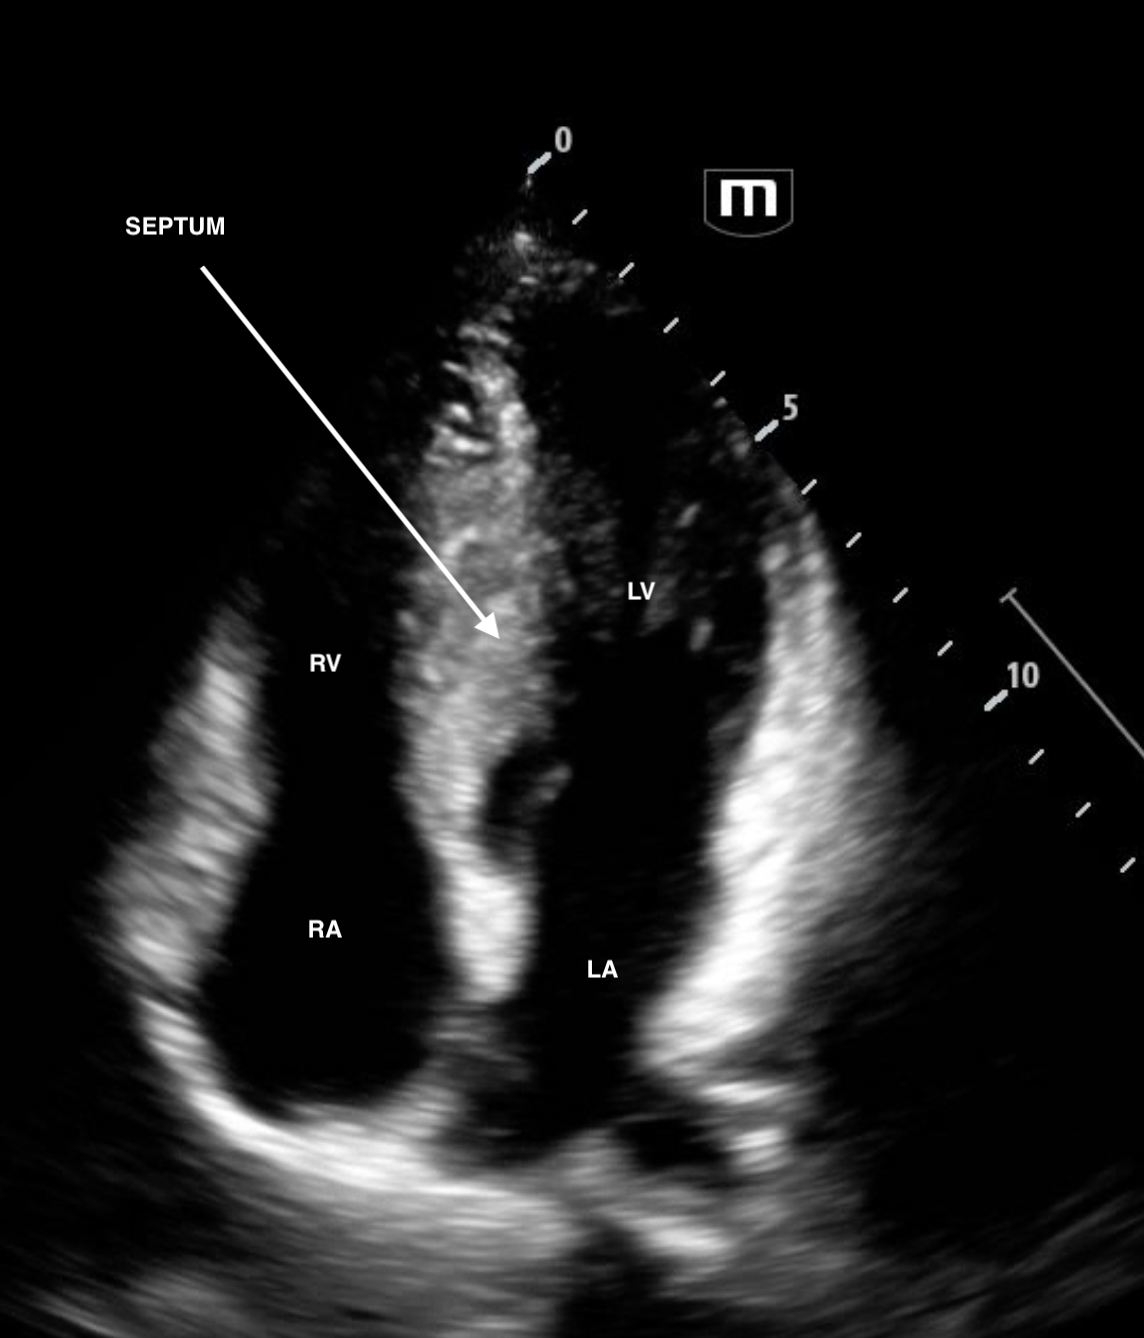

A4C

The patient was admitted to cardiology. Formal echo revealed septal thickness of 3.2cm (normal <1cm). RV inflow was turbulent with a Vmax 4.2m/s (!!!!!!!) Mean 30mmHg and Peak Gradient of 69mmHg. For context, normal RV inflow ie flow across the tricuspid valve has a Vmax <0.7m/s.

The high Vmax shows that there is obstructed flow across the TV: acting like a tricuspid stenosis. This leads to impaired RV filling. Hence the patient's syncope with the vagal episode or with acute volume loss.

Typically septal hypertrophy affects the LV side of the septum. But in this case, it's bulging into the RV.